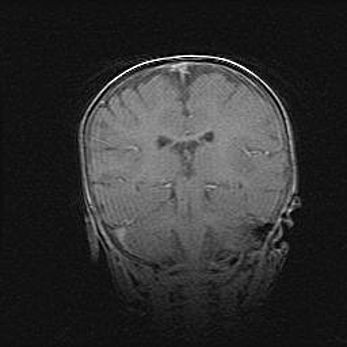

Сообщающаяся гидроцефалия. Кистозная энцефаломаляция головного мозга.

Возраст: 3 месяца 4 дня

Вес: 3100 г

Пол: женский

Окружность головы: 34 см

Срок гестации: 31 неделя

Кистозная энцефаломаляция головного мозга - одна из форм поражения головного мозга в детском возрасте. Характеризуется возникновением множественных и распространённых кист в коре, белом веществе и подкорковых образованиях головного мозга у плодов, новорождённых и детей раннего возраста. Развитие кистозной энцефаломаляции связано с внутриутробной асфиксией и гипотонией, родовой травмой, тромбозом синусов, пороками развития сосудов, инфекциями, сепсисом и другими причинами. Наиболее значимые инфекционные агенты: вирусы простого герпеса, цитомегалии, краснухи, токсоплазмы, энтеробактерии, золотистый стафилококк и другие.